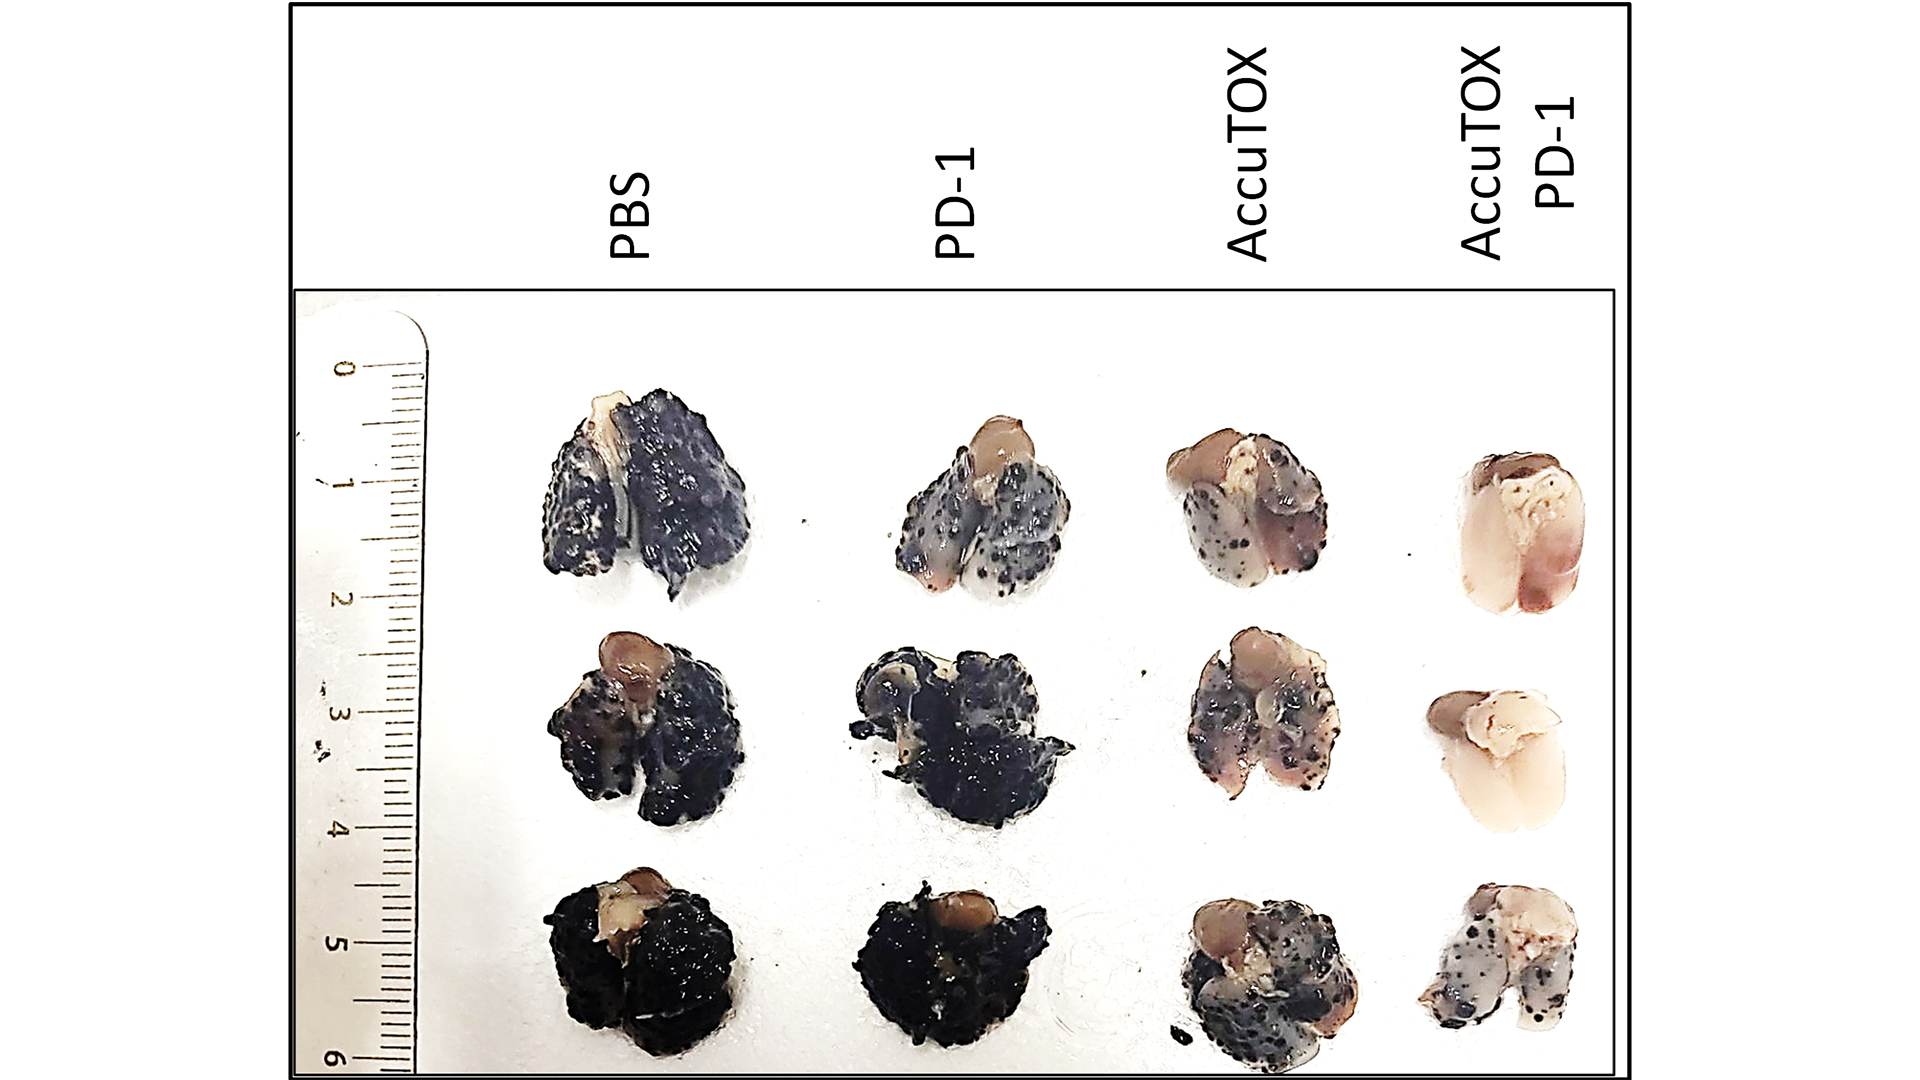

When administered as a monotherapy, AccuTOX® showcased its ability to inhibit the growth of lung nodules, signifying its potential as a standalone treatment against this form of cancer.

These effects were amplified when combined with the immune-checkpoint inhibitor anti-PD1, shown in Figure 1 below.